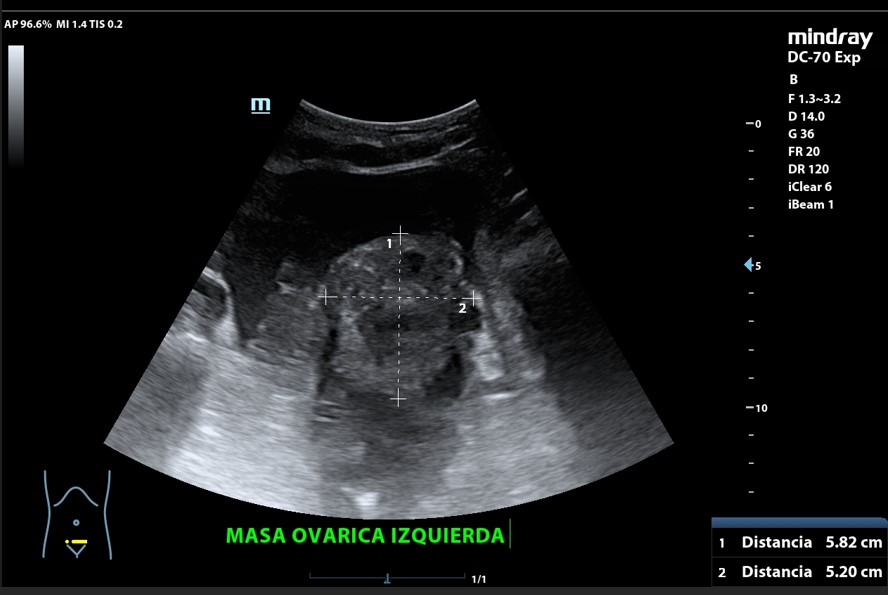

Presencia de 2 masas pélvicas bien delimitadas heterogéneas que captan Doppler, una de 5 cm de diámetro y otra ovalada de 10 cm de longitud. Líquido ascítico peritoneal, que también se observa alrededor del bazo y en espacio de Morrison. Derrame pleural derecho.

Tumoración ovárica bilateral.